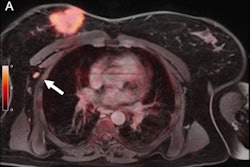

In other news, a group from Dusseldorf in Germany has found that FDG-PET/MRI outperformed ultrasound and MRI for the detection of axillary lymph node metastases in breast cancer cases. When combined with ultrasound, the hybrid technique may also boost accuracy and avoid the need for invasive biopsies, they said.